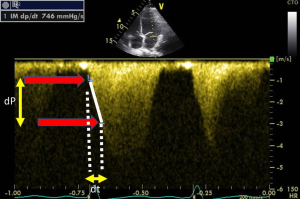

dP/dt on mitral regurgitation

We demonstrated that all volunteers, in whom we performed TTE, a small mitral regurgitation was present (23) V体育官网. Because mitral regurgitation velocity changes during systole is related to the change of intra ventricular pressure, dP/dt could be easily assessed this flow recorded using continuous wave Doppler (Figure 5). By measuring the duration time (dt) between the velocity of 1 m/s and the velocity of 3 m/s (dP of 32 mmHg) on the mitral regurgitation envelop it becomes easy to diagnose any LV systolic dysfunction (normal ranges 800–1,200. This approach was well validated (24,25).